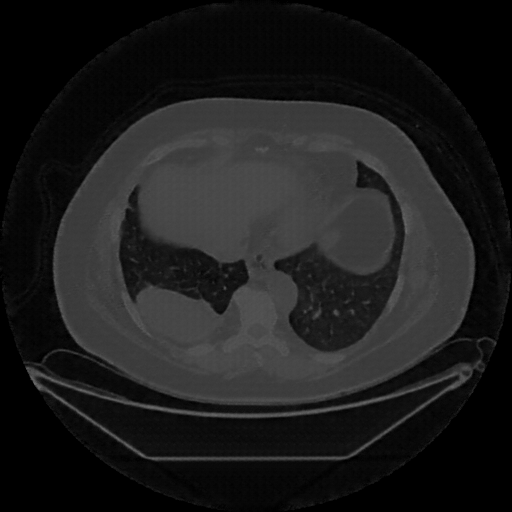

Image Grid

4Γ—3 grid: Rows show different image types (Original NATIVE, Reconstructed NATIVE, Original VENOUS, Generated VENOUS), Columns show windowing techniques (No Window, Lung Window, Mediastinum Window)

Reconstructed NATIVE CT scan (cycle consistency)

No window - Raw intensity values

Lung window (WL -600, WW 1500 β†’ Low βˆ’1350, High +150)

Mediastinum window (WL 40, WW 400 β†’ Low βˆ’160, High +240)